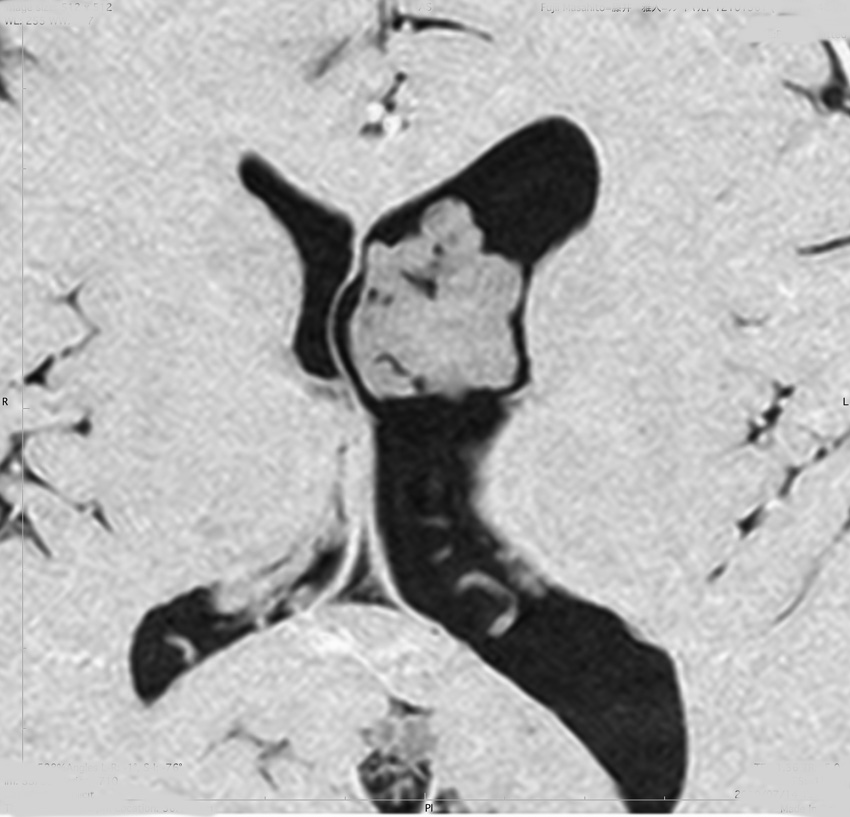

無症状で偶然発見された47歳女性の側脳室内上衣下腫

無症候で偶然発見された左側脳室前角尾状核頭に接したsubependymoma。定位脳生検で病理診断を得たましたが,3年間の観察で徐々に増大しました。左上が発見時,1年後(右上),2年後(左下),3年後(右下)

CTではやや低吸収,T1ガドリニウムでは低信号となりガドリニウム増強されません。小さな上衣下腫の場合は等吸収あるいは等信号のものも多いです。小さく点状に造影されている部分があるがこれは定位脳手術痕(track)です。

左中前頭回からの経皮室法 left middle frontal gyrus transcortical approach で全摘出できました(右図)。